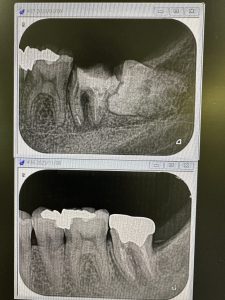

午前の定期検診

もう駄目かなあ?と考えていたが、自然治癒力は素晴らしい

愛用している、特級水酸化カルシウム、カルビタール

症例に応じて使い分け

メーカー発売製品は効能が乏しい、元昭和大学歯学部歯内療法科松本光吉教授の教え!🤪

貼薬剤だけでは駄目、他諸々技術あり、それは秘密㊙️🤫

本医院では、保険治療でさえ純度100%のガッタパーチャー使用、術式殺菌レベルが違うのにね🤪